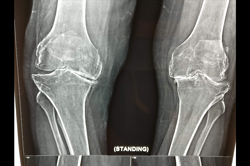

Osteoarthritis – High Tibial Osteotomy - HTO